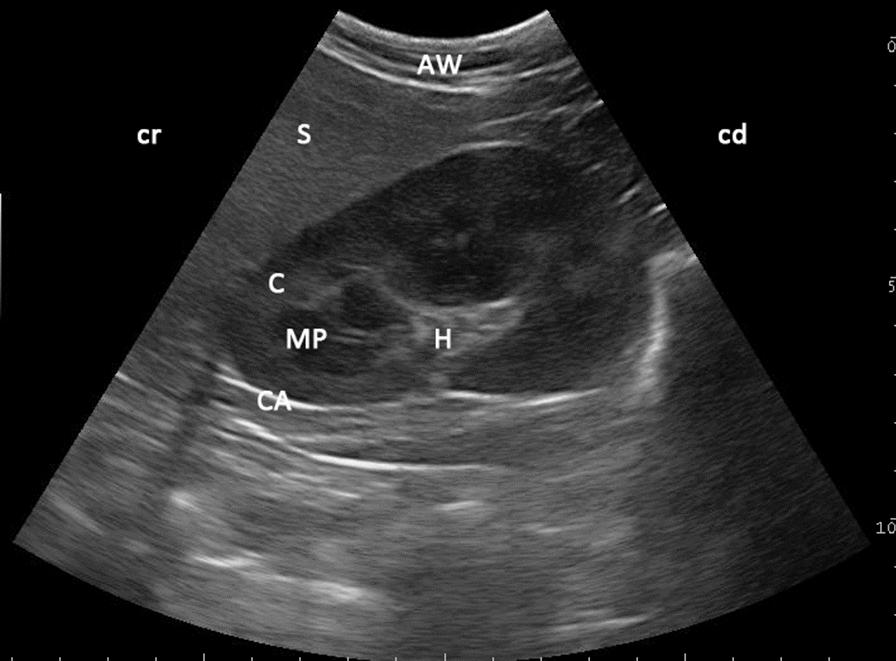

RESULTS

Ultrasonography was performed in 135 clinically healthy, non-sedated llamas and alpacas. Screening was performed with a 6.6 MHz curve linear transducer with only alcohol as contact medium between the probe and unclipped skin. The kidneys could be imaged from the paralumbar region. The right kidney only was visualized when scanning from the right and the left kidney only from the left. While the left kidney appeared in sagittal view as an oval shape in most llamas and alpacas, in one third of animals the left kidney had a triangular shape. The L-shaped base of the spleen, with its homogeneous, echoic pattern, could be seen craniolateral to the left kidney. Anechoic areas displaying vessels inside the spleen and a thin echoic capsule surrounding the splenic tissue could be differentiated. While sonographic appearances of the examined organs showed no differences between llamas and alpacas, selected dimensions of both of kidney and spleen showed significant differences between species. In terms of age and sex, significant differences in respect of kidney size could be found only in alpacas. Sex seemed to have no influence on kidney and spleen sizes in llamas.

本研究对 135 只临床健康、未镇静的羊驼进行了超声检查。使用 6.6MHz 线阵探头,仅以酒精作为探头和未修剪皮肤之间的接触介质进行筛查。可以从腰部旁区域对肾脏进行成像。从右侧和左侧仅能分别显示右侧和左侧的肾脏。虽然大多数羊驼的左肾在矢状视图上呈椭圆形,但三分之一的动物的左肾呈三角形。脾脏的 L 形基底,具有均匀的回声模式,可在左肾的颅侧看到。可以区分脾脏内显示血管的无回声区和围绕脾脏组织的薄回声包膜。虽然检查器官的超声表现没有显示出羊驼和羊驼之间的差异,但肾脏和脾脏的选定尺寸在种间存在显著差异。就年龄和性别而言,仅在羊驼中发现肾脏大小存在显著差异。性别似乎对羊驼的肾脏和脾脏大小没有影响。